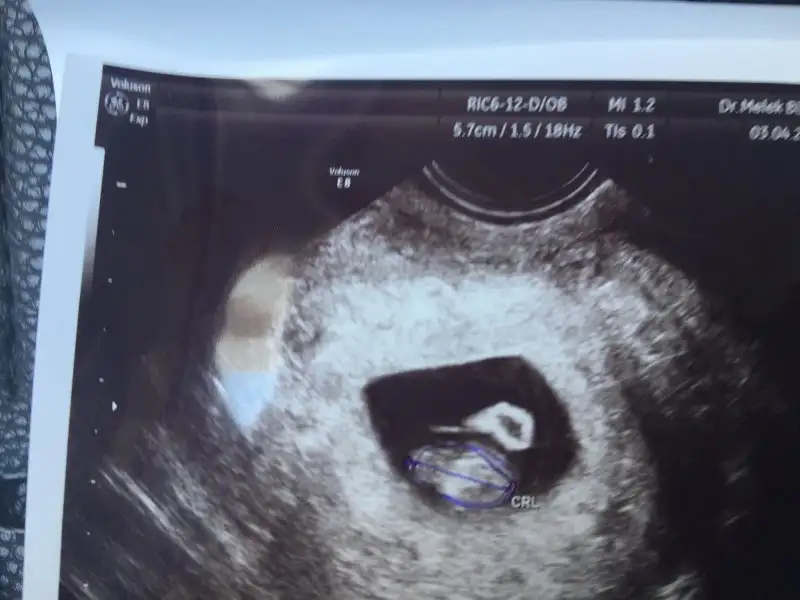

buna gore erkek canım. benım karından boyleydı doktor kıza benzıyor dedı. kesındegıl benımkıde ama kesnlesırse teorı bnde tuttuEki Görüntüle 1939188 Eki Görüntüle 1939187 Kizlar banada baksanizaa altan utrasyon yani vajenden

6+3 falan karindan :) plesanta nerede ya kiz mi erkek miyardimmmmm